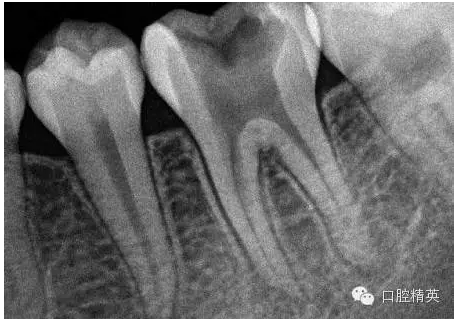

1,術(shù)前X-ray,常規(guī)術(shù)前攝片,

為患者和自己保留一份客觀記錄。。。

3,術(shù)前左下6近中根管斷針X-P,斷針長(zhǎng)度約4MM,根尖慢性炎癥影像。。。